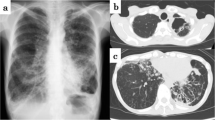

The initial BAL specimen (HD10) was confirmed as M. kumamotonensis by hsp65 gene amplification and sequencing of the 441 base-pair fragment with alignment to known sequences in GenBank (https://www.ncbi.nlm.nih.gov/genbank/) on HD30 and 16S rRNA gene amplification was also performed and aligned to known sequences in GenBank for further confirmation (Fig. 2). Phylogenetic trees were generated from alignment results using Lasergene MegAlign Pro software from DNASTAR, Inc. (DNASTAR, Madison, WI USA). Antimicrobial susceptibility testing was performed at National Jewish Medical Center (Denver, CO), with the following results: Rifabutin (S), Moxifloxacin (R), Amikacin (I), Linezolid (R), Ciprofloxacin (R), Streptomycin (NI), Clarithromycin (S), Rifampin (R), Ethambutol (NI); Rif + Etham (NE), Rifampin combo (TI), Ethambutol combo (TS); Doxycycline (R), Trimethoprim-sulbactam (S), Clofazimine (NI), Minocycline (R) (S = susceptible, R = resistant, NI = no interpretation, NE = no effect, TI = tentative intermediate, TS = tentative susceptible). The patient’s initial therapy was oral azithromycin, ethambutol and intravenous amikacin based on the organism identification. Once susceptibility results were available, therapy was modified to ethambutol, azithromycin, and rifabutin for 6 months from first negative AFB culture. The patient continued to tolerate the regimen well with no adverse effects, aside from possible renal toxicity detected via changes in creatinine clearance, which was addressed by subsequent reductions in the weekly ethambutol dosage. The patient underwent dose adjustment of the tacrolimus used in his immunosuppression regimen once initiated on rifabutin.

Phylogenetic trees for the members of Mycobacterium terrae complex, based on 16S rRNA (1487 bp) and hsp65 genes (441 bp). The sequence of 16S rRNA and hsp65 genes show 99.5% (1421/1424 identities) and 99.1% similarity (420/424 identities) compared with reported sequences of M. kumamotonensis (strain CST7274) [15]. hsp65 gene shows 100% (409/409 identities) match with M. kumamotonensis S1-30